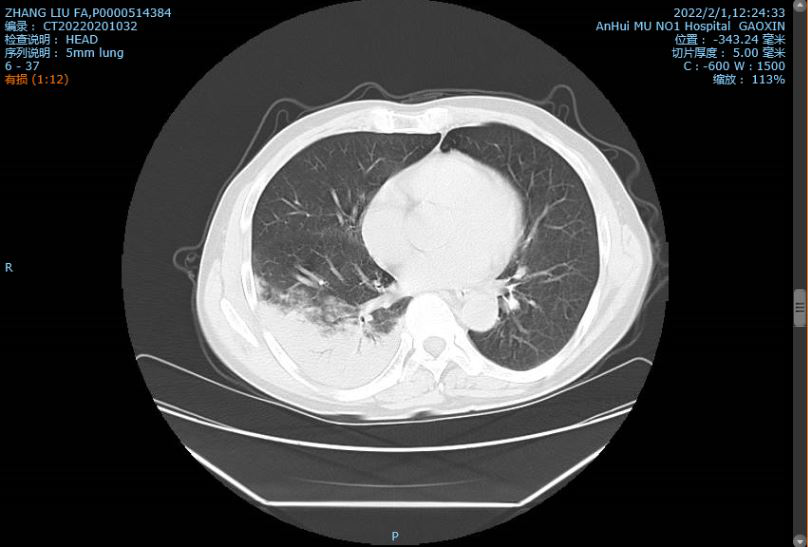

张勇(化名)肺部出现感染。